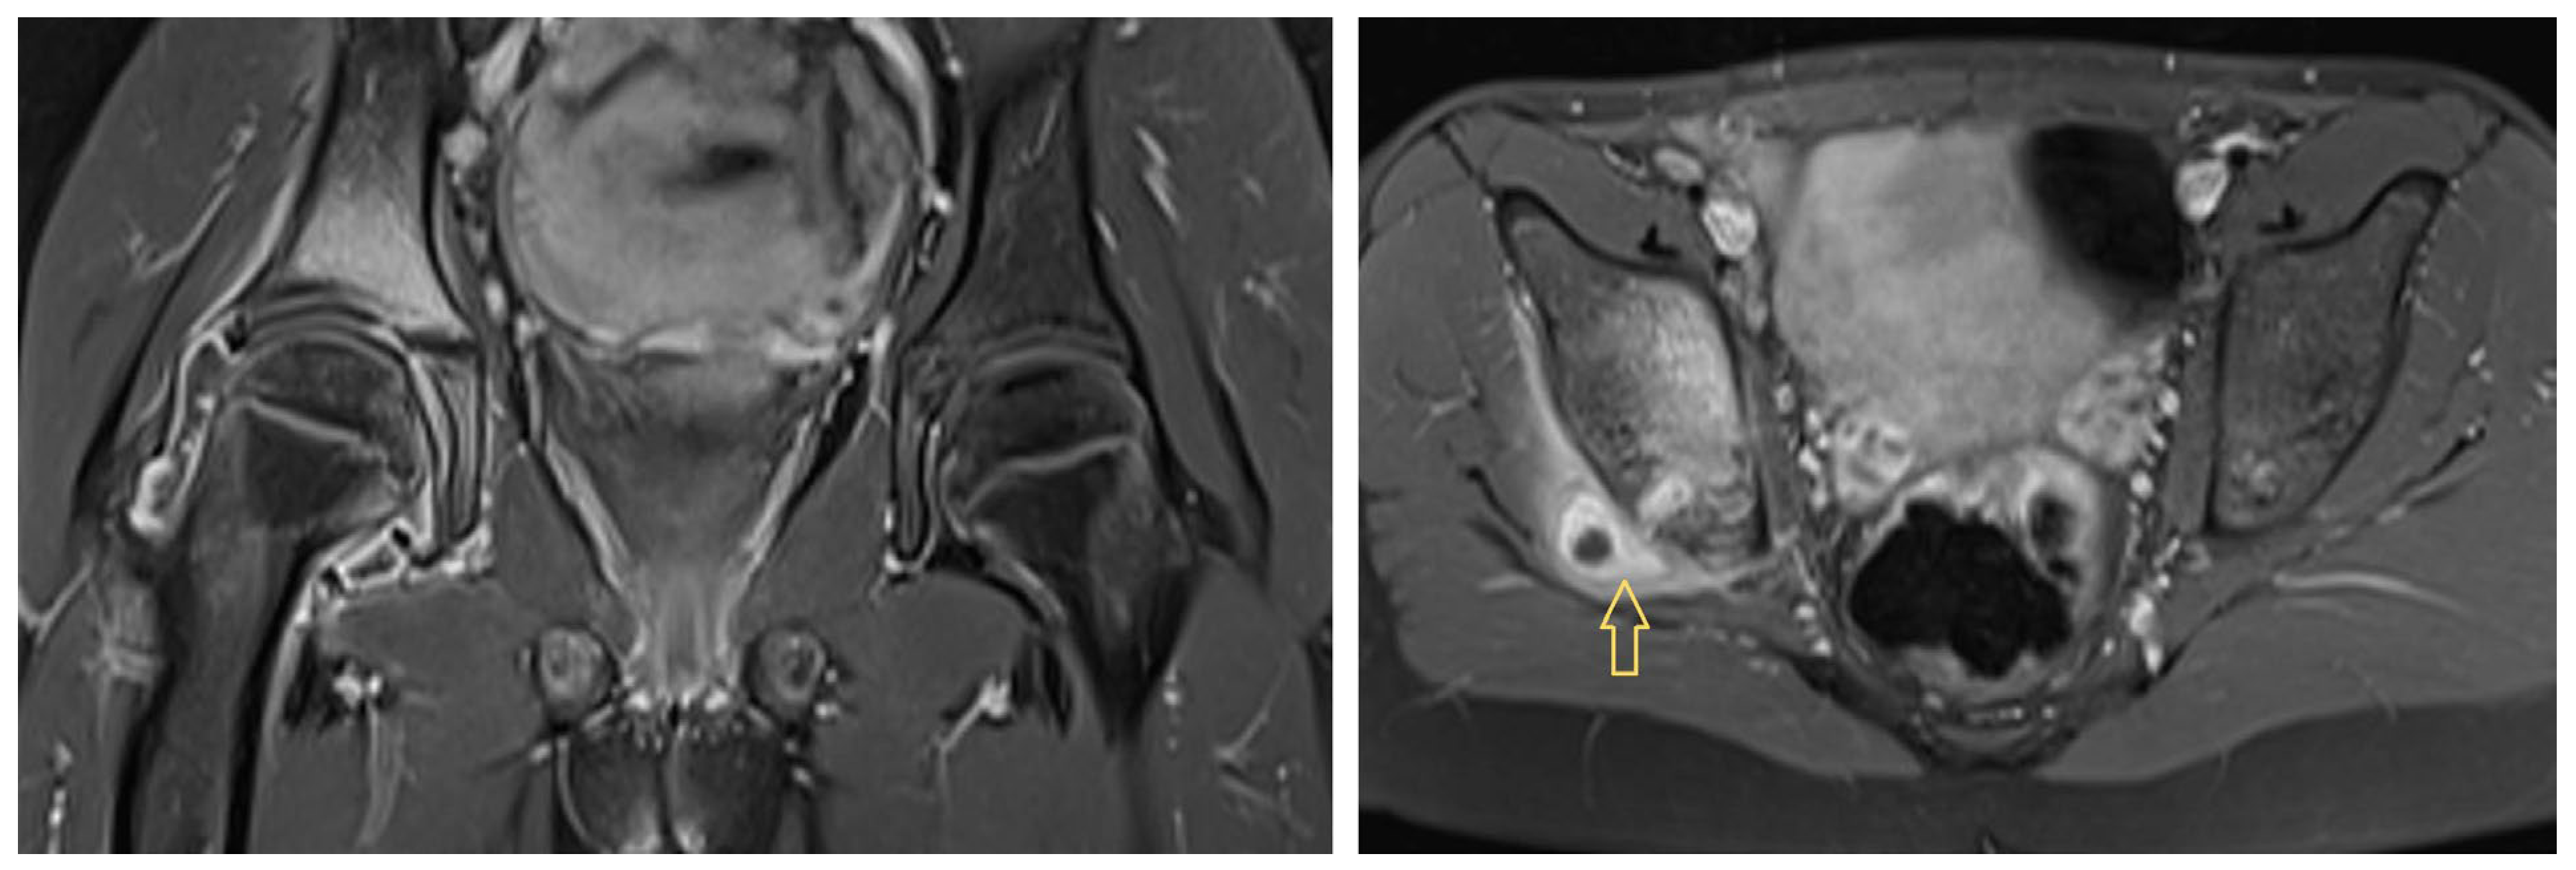

3.1.1. Patient 1

3.1.2. Patient 2

3.1.3. Patient 3